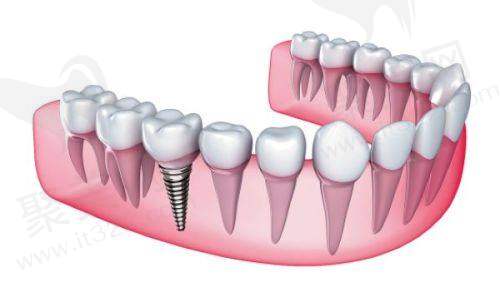

种牙,简单来说,就是把人工牙根植入牙槽骨内,等人工牙根和牙槽骨长在一起后,再安装上牙冠,这样就完成了牙齿的修复。这个人工牙根就相当于真牙的牙根,能给牙冠提供稳定的支撑,让牙齿就像真牙一样结实耐用。

烤瓷牙是通过把缺失牙两边的健康牙齿磨小,然后做一个连冠套在磨小的牙齿上,以此来修复缺失的牙齿。它主要是依靠两边的基牙来固定和支撑,就像搭桥一样,所以也叫烤瓷桥。

2. 不损伤邻牙:种牙不需要磨损旁边的健康牙齿,能较大程度地保留自己的真牙。这就好比盖房子,不用拆了旁边的房子来给自己的房子打基础,对牙齿的整体结构和健康影响较小。